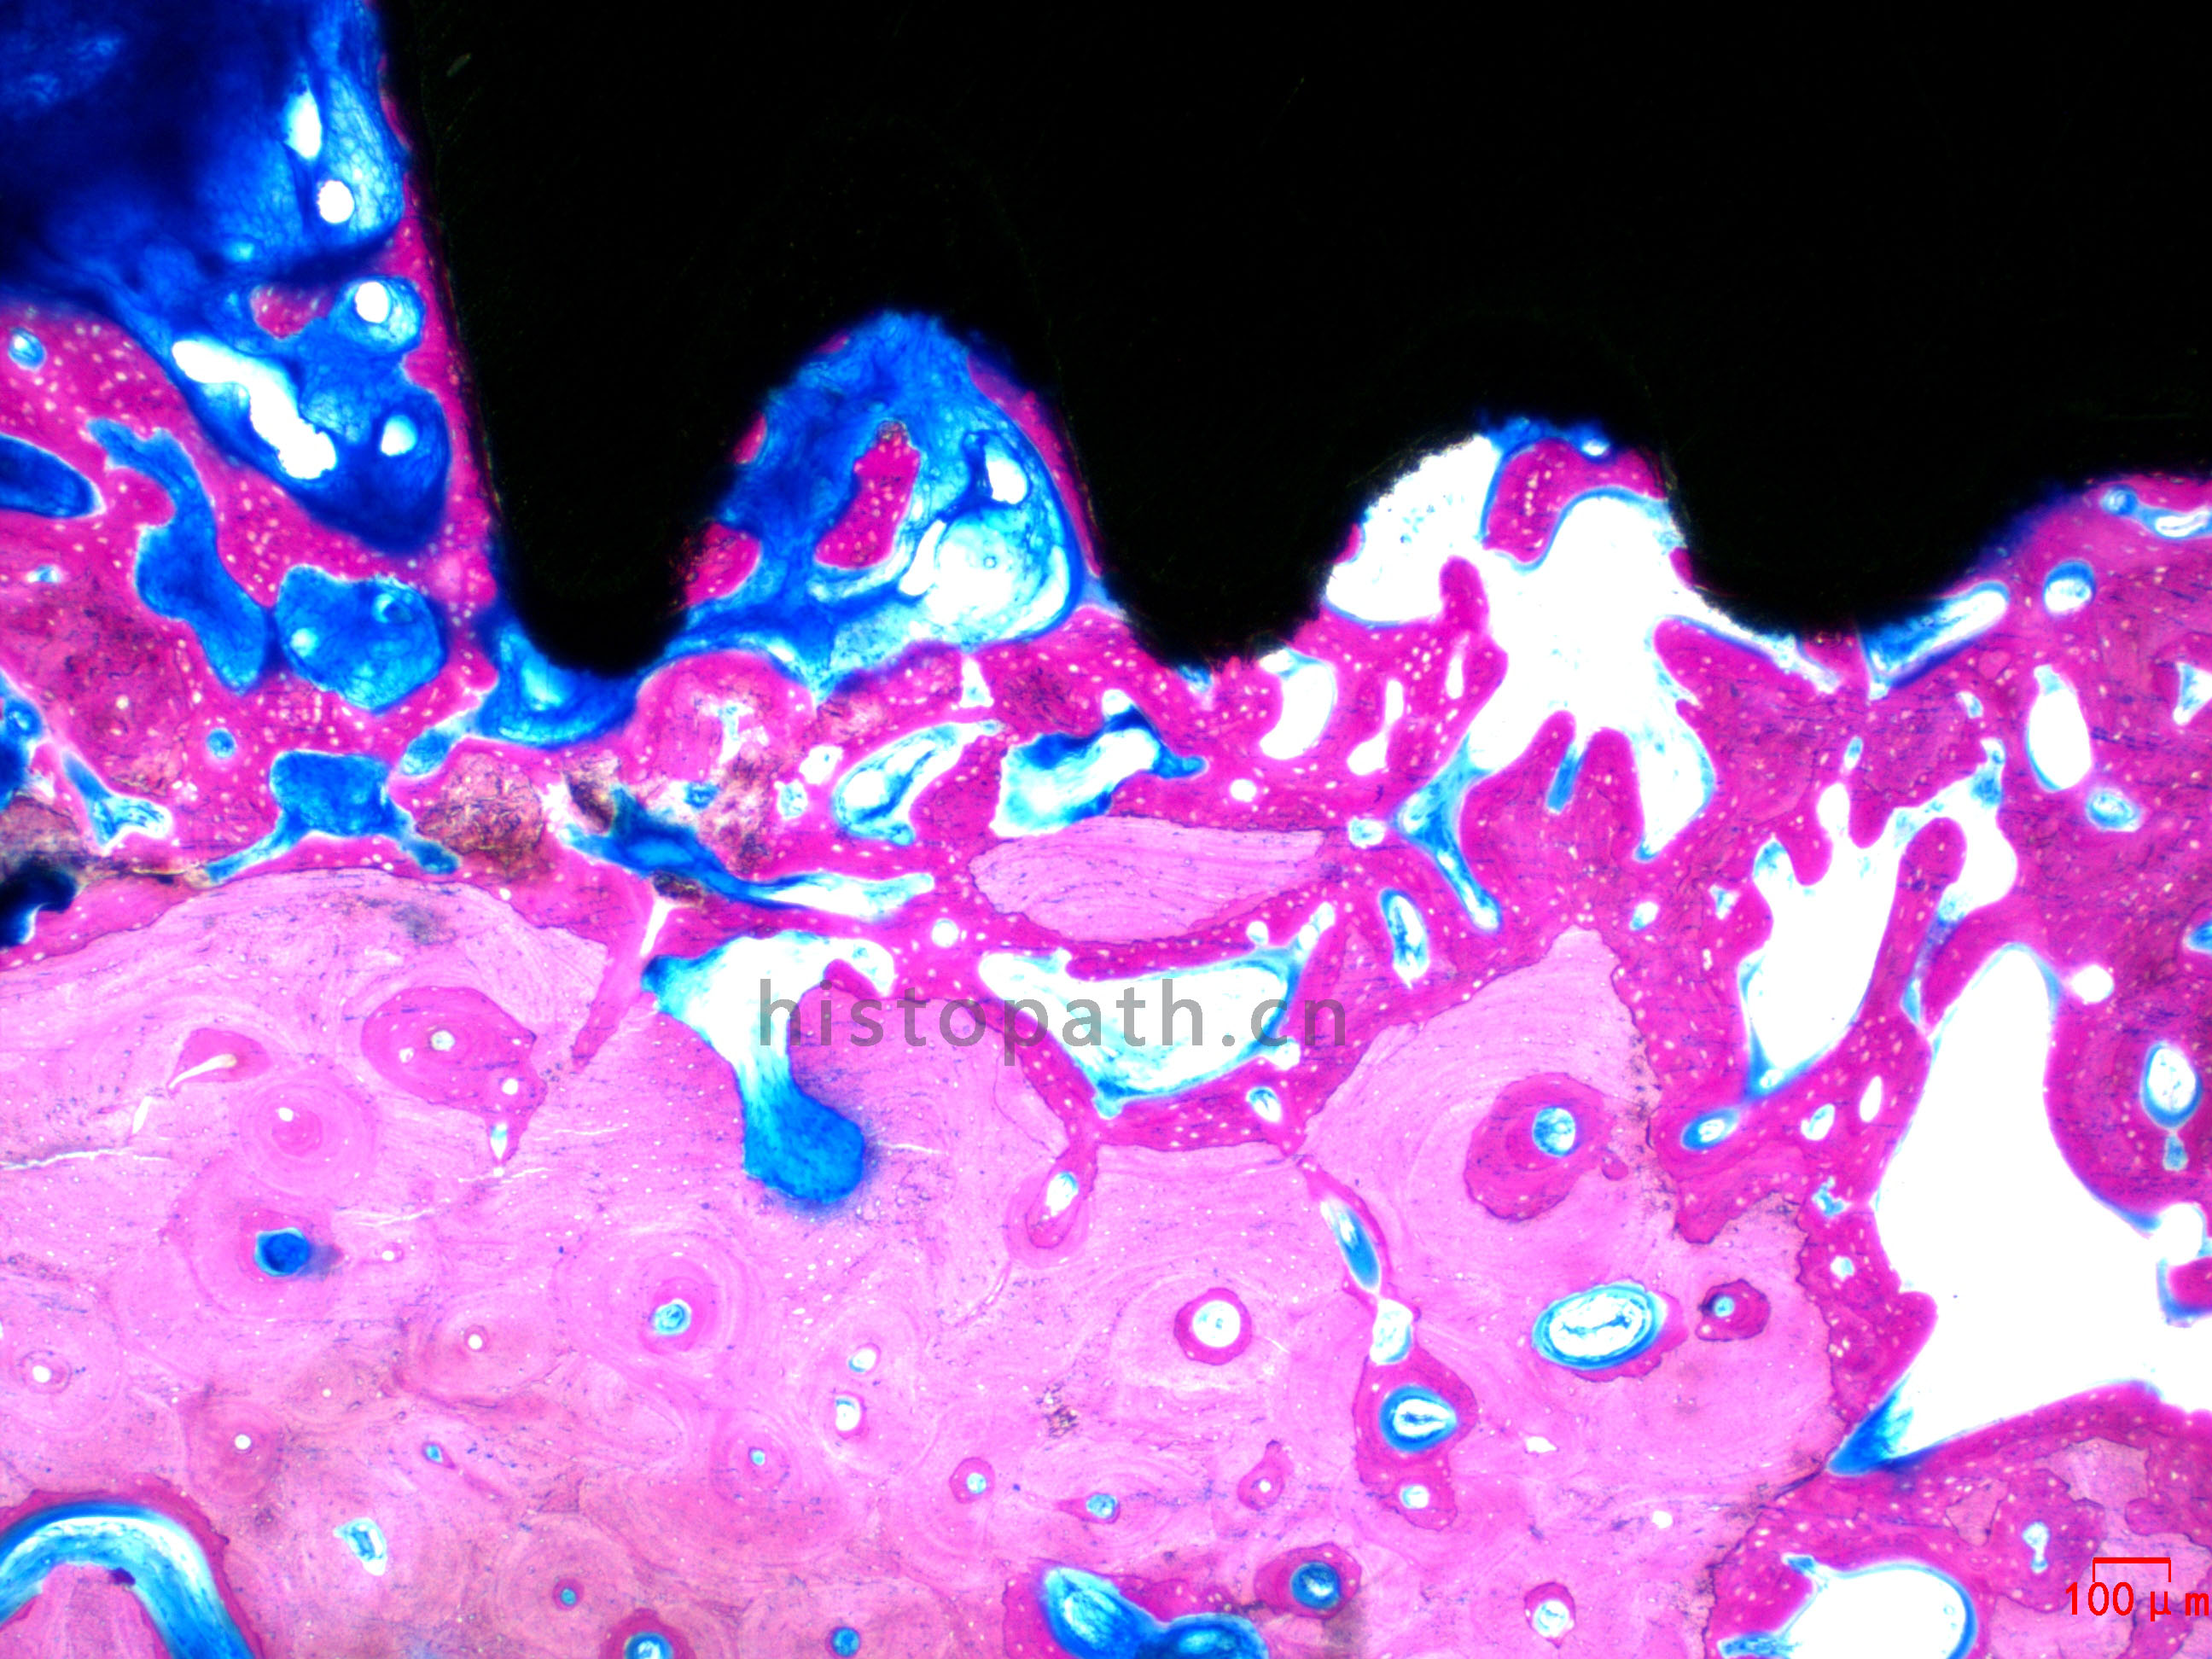

牙体种植:亚甲基蓝--酸性品红染色

牙种植体亚甲基蓝酸性品红染色.jpg

使用德国EXAKT切磨系统进行硬组织切片,特别是对于含有金属这类植入物的组织,是一种精确的组织切片技术。

各类尺寸的含金属植入物骨、牙齿、血管等硬组织样本脱水,7200树脂浸润包埋,后期用标准尺寸(25mm*75mm)的树脂片进行切磨片处理。

将包埋好的硬组织树脂块,用EXAKT 硬组织切片机先切一个200um的厚片,然后再通过EXAKT 硬组织磨片机将其磨到20-30um薄片,样本是已经硬组织包埋好的含金属的动物样本。

针对不同的病理阅片指标需求,行HE染色、Masson染色、亚甲基蓝-酸性品红染色、VG染色、Movat染色等。